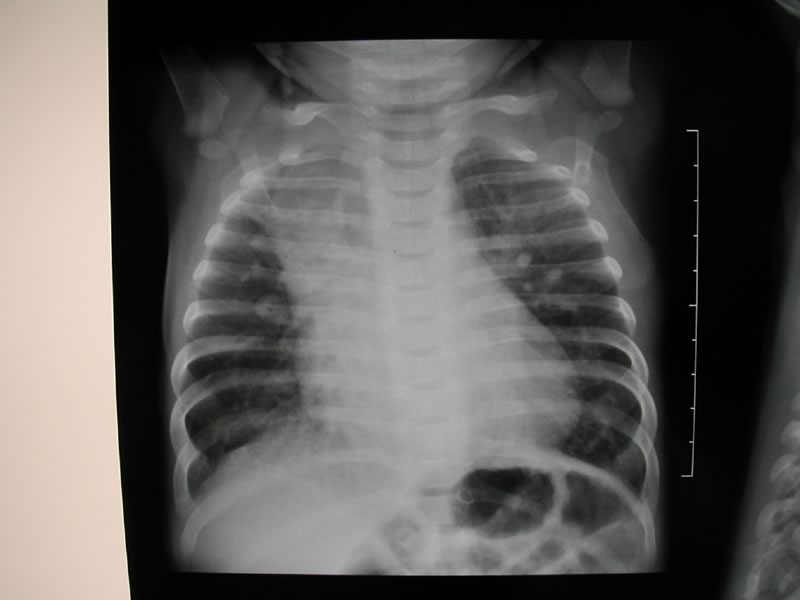

L'ecocardiografia evidenzia la presenza di un difetto interventricolare sottoaortico tra aorta e tricuspide con diametro superiore al 50% dell'aorta (Fig. 2), senza alcuna copertura aneurismatica, con sovraccarico di volume del ventricolo e dell'atrio sinistro; al color doppler ampio jet sinistro-destro a bassa velocità suggestiva per elevata pressione in ventricolo destro (Fig. 3).